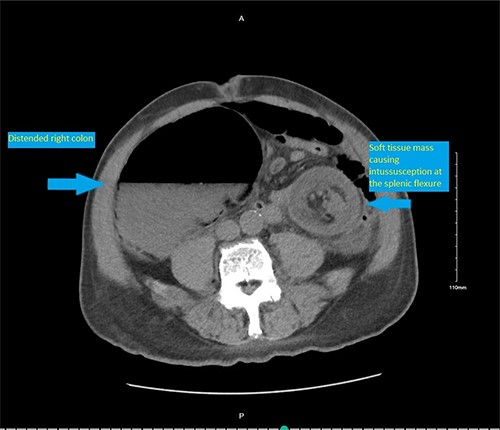

On presentation, the patient was afebrile with stable vital signs. Physical exam was significant for a markedly distended abdomen with generalized tenderness, worse on the left side with resonance on percussion. There were no abdominal hernias. The digital rectal examination revealed no lesions. The rectal tone was good and there was no stool in the vault. Laboratory evaluation showed hypokalemia (3 mmol/L) and mild anemia (hemoglobin 13.1 g/dl).A computed tomography (CT) scan of abdomen and pelvis was performed and showed colonic intussusception in the descending colon with a possible lipoma/ fat containing lesion associated with the wall of the distal left colon and proximal sigmoid colon measuring 4.2 cm × 4.3 cm (Figs 1–3). There was marked distended right colon and transverse colon but no sign of bowel perforation or free air seen. There is mucosal thickening of the left colon with pericolic stranding. Developing ischemia of the left colon could not be ruled out. With the findings on imaging, it was determined that the patient would undergo an exploratory laparotomy with left hemicolectomy to remove the intussuscepted bowel.

CT scan scout showing distended colon proximal to a soft tissue mass/ shadow at the splenic flexure.

CT scan pelvis (axial cut) showing a soft tissue lesion in the left colon, with surrounding fat stranding and distended right colon.

CT scan pelvis (axial and coronal cuts) showing a soft tissue lesion in the left colon, with surrounding fat stranding and distended right and transverse colon.